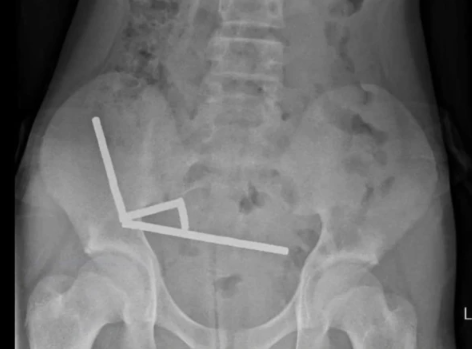

نیوزی لینڈ میں ایک 13 سالہ لڑکا تقریباً 80 سے 100 انتہائی طاقتور نیوڈیَمِیم (neodymium) مقناطیسی گولیوں کو نگل گیا۔ یہ گولیاں ایک آن لائن مارکیٹ پلیس (رپورٹ کے مطابق Temu) سے خریدی گئی تھیں۔ بچے کو چار دن تک معدے / پیٹ میں درد رہا، پھر اسپتال لایا گیا جہاں ایکس رے سے مقناطیسوں کی زنجیری شکلوں کا مشاہدہ ہوا جنہوں نے مختلف حصوں میں جمع ہو کر نقصان پہنچایا ہوا تھا۔

لڑکے کی سرجری کی گئی اور مقناطیسوں کے ساتھ ساتھ آنتوں کے اس حصے کو نکالنا پڑا جہاں ٹشوز شدید نقصان کا شکار ہوئے تھے۔ طبی ماہرین نے اس واقعے کو “بچوں کے لیے انتہائی خطرناک” اور بالخصوص آن لائن دستیابی کی وجہ سے ’لازمی روکا جانے والا اقدام‘ قرار دیا ہے۔